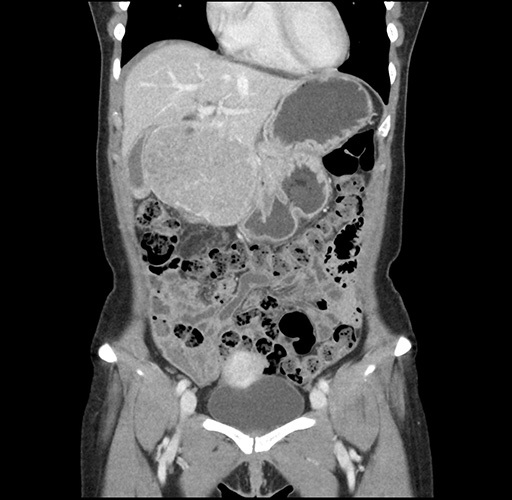

Imaging Analysis

Look through the patient's CT scan to identify any areas of concern for the necessary procedure.

Based on your CT findings, which issue(s) would give reason for "planned slowing down moment(s)" in this case?

Considering a standard left lateral sectionectomy procedure, what step(s) of the operation would you do differently in this case ?